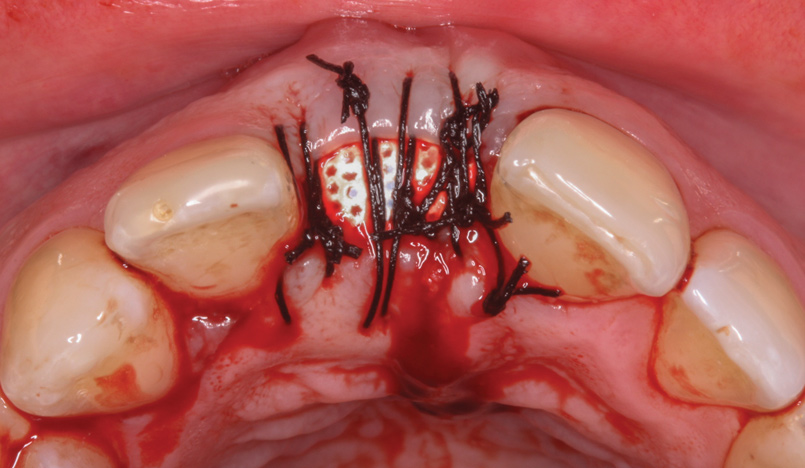

A d-PTFE (Cytoplast) barrier was trimmed into the shape of an ice cream cone to conform to the socket's morphology (Figure 4). The barrier was placed inside the alveolus and compressed laterally into the buccal dehiscence (Figure 5). Small-particle, mineralized cancellous freeze-dried bone allograft (ie, 0.25 mm to 1 mm) was inserted into the socket and packed against the barrier. The socket was filled 1 mm to 2 mm above the alveolar crest to aid in attaining a convex rather than concave gingival architecture at the socket opening upon removal of the barrier. The barrier was tucked under the palatal flap (3 mm) and secured with Vicryl 4-0 single interrupted sutures (Figure 6 through Figure 8).

Fig 8. The barrier was secured by interrupted sutures.

Figure 8